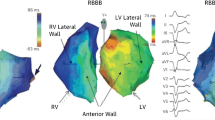

The presence of left bundle branch block morphology is a strong predictor of response to CRT [18]. Whilst no definitive data exists evaluating CRT response in patients with right bundle branch block (RBBB), retrospective analysis suggests that this group of patients tends to do less well. Interestingly, when patients with heart failure and RBBB were analysed using 3D non-contact mapping, they were found to exhibit significant LV activation delay in addition to the delay identified in the RV [19]. In addition, LBBB activation is not exclusively associated with electrical conduction delay [20]. In one analysis, up to a third of patients with LBBB who underwent electromechanical or non-contact mapping demonstrated normal trans-septal activation time and a near-normal LV endocardial activation time [21]. It is possible that more nuanced assessments of electrical delay, such as non-invasive body surface mapping, may be able to detect remediable patterns of electrical delay with greater accuracy.